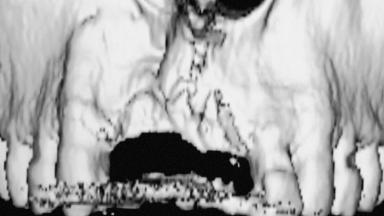

Bone Augmentation Horizontal|Staged|Vertical

Augmentation Materials Autogenous chips|Autogenous block(s)

Bone Volume Deficient vertically or deficient vertically AND horizontally